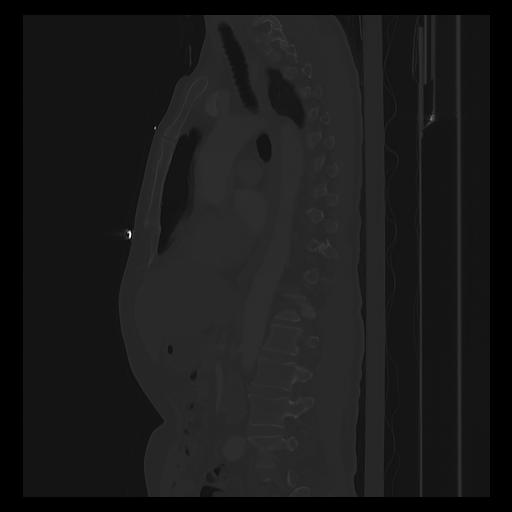

33 PULMON,CE,Sagittal,3.000,PULMON,Sagittal,